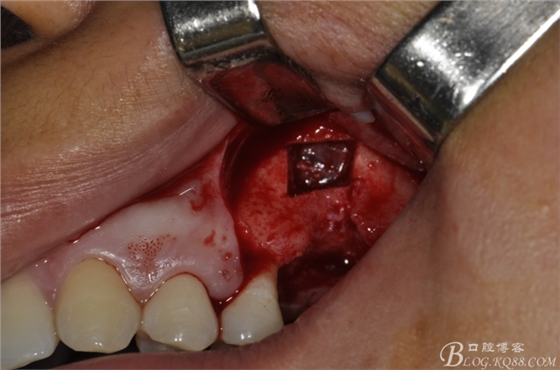

術(shù)中照片。